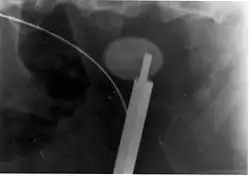

A kidney stone at the tip of an ultrasonic stone disintegration apparatus

More definitive ureteroscopic techniques for stone extraction (rather than simply bypassing the obstruction) include basket extraction and ultrasound ureterolithotripsy. Laser lithotripsy is another technique, which involves the use of a holmium:yttrium aluminium garnet (Ho:YAG) laser to fragment stones in the bladder, ureters, and kidneys.[118]

Ureteroscopic techniques are generally more effective than ESWL for treating stones located in the lower ureter, with success rates of 93–100% using Ho:YAG laser lithotripsy.[85] Although ESWL has been traditionally preferred by many practitioners for treating stones located in the upper ureter, more recent experience suggests ureteroscopic techniques offer distinct advantages in the treatment of upper ureteral stones. Specifically, the overall success rate is higher, fewer repeat interventions and postoperative visits are needed, and treatment costs are lower after ureteroscopic treatment when compared with ESWL. These advantages are especially apparent with stones greater than 10 mm (0.4 in) in diameter. However, because ureteroscopy of the upper ureter is much more challenging than ESWL, many urologists still prefer to use ESWL as a first-line treatment for stones of less than 10 mm, and ureteroscopy for those greater than 10 mm in diameter.[85] Ureteroscopy is the preferred treatment in pregnant and morbidly obese people, as well as those with bleeding disorders.[7]